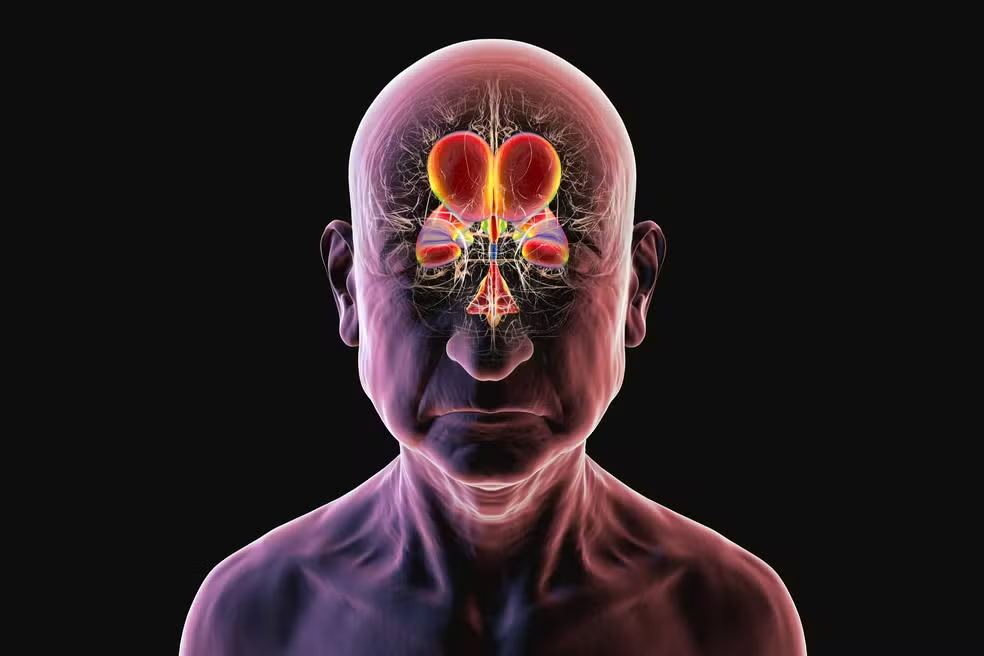

Nos casos de HPN, o líquor deixa de circular e de ser reabsorvido adequadamente. Os ventrículos cerebrais — cavidades cheias de líquido — aumentam de tamanho e passam a comprimir estruturas vizinhas. Essa pressão crônica interfere no funcionamento de circuitos neurológicos profundos ligados à marcha, ao controle postural e às funções executivas – as habilidades mentais associadas ao lobo frontal, responsáveis por planejar, manter a atenção, controlar impulsos, reter informações temporariamente e adaptar-se a novas situações.

No estudo referido, as imagens cerebrais obtidas por exames como a ressonância magnética mostraram uma redução do volume dos ventrículos após o início do funcionamento da válvula, indicando que o tratamento não atua apenas sobre os sintomas, mas modifica a mecânica interna do cérebro.

Menor distensão ventricular significa menos estiramento de fibras nervosas profundas, especialmente na substância branca periventricular. Essas fibras funcionam como verdadeiras “autoestradas”, conectando regiões frontais a centros motores e ao controle esfincteriano. a comunicação entre essas áreas se torna menos eficiente quando elas são comprimidas.